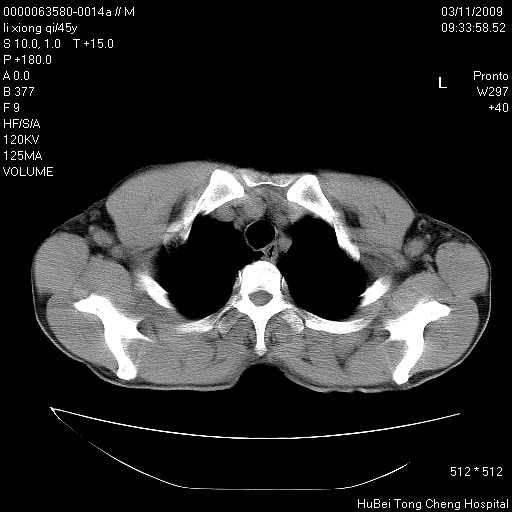

患者 男,45岁。胸痛,咳嗽伴痰中带血1月余。

临床诊断:肺结核?

胸部ct轴位平扫(层厚10mm,螺距1.5,重建间隔10mm),图像如下: